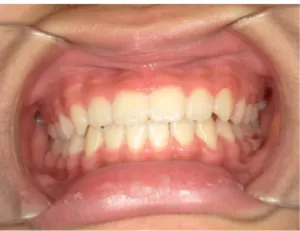

治療中③小2(7y8m):JUMP 受け口が改善

治療中④小2(8y2m)~小3(9y1m):QHとBHで拡大・アーチ形態の修正、ブラケットで前歯の並べ替えまで終了

| 行ったご提案・診断内容 | 成長期に行う治療と咬合治療をご提案 受け口用ファンクショナルアプライアンス(写真②③)からスタートし、小2以降で上下顎の拡大・歯列弓の形態修正・前歯の並べ直し(写真④)を行いその後、モノブロック(筋機能的咬合誘導)装置(写真⑤)へ移行し、受け口の再発予防と永久歯を適切な咬み合わせに誘導し、必要によりマルチブラケット法へ移行する治療方法を提案しました。 成長期治療(成長時期にお口の環境を整える治療) 2年生以降から 咬合治療 |

| 治療期間 | 12か月:受け口用ファンクショナルアプライアンス(写真②③) 12カ月:成長期治療の動的治療期間(写真④) 現在、成長の経過観察と咬合誘導中です(写真⑤~⑨) |